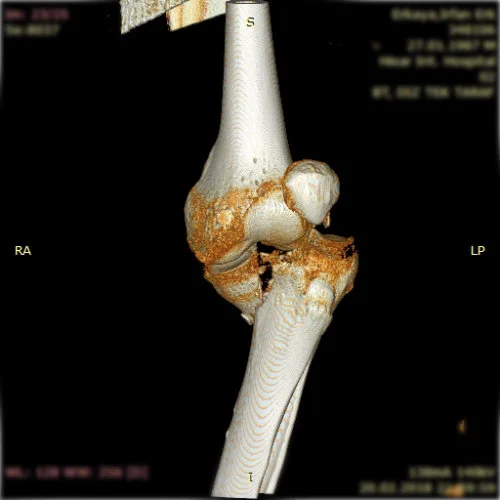

Kas-iskelet sisteminin tüm kırık ve çıkıkları, kas, tendon ve sinir yaralanmaları geniş bir yelpazeyi kapsamaktadır. Her kırık kendi özelinde ayrı ayrı değerlendirilmeli ve her kırık için ameliyat planlaması bu bağlamda yapılmalıdır. Özellikle pelvis-asetabulum kırıkları ortopedik travmada bizler için önemli bir yer tutmaktadır. Bu bölge kırıklarını başarı ile tedavi etmekteyiz.

Görüntüleri büyütmek için resmin üstüne tıklayınız.